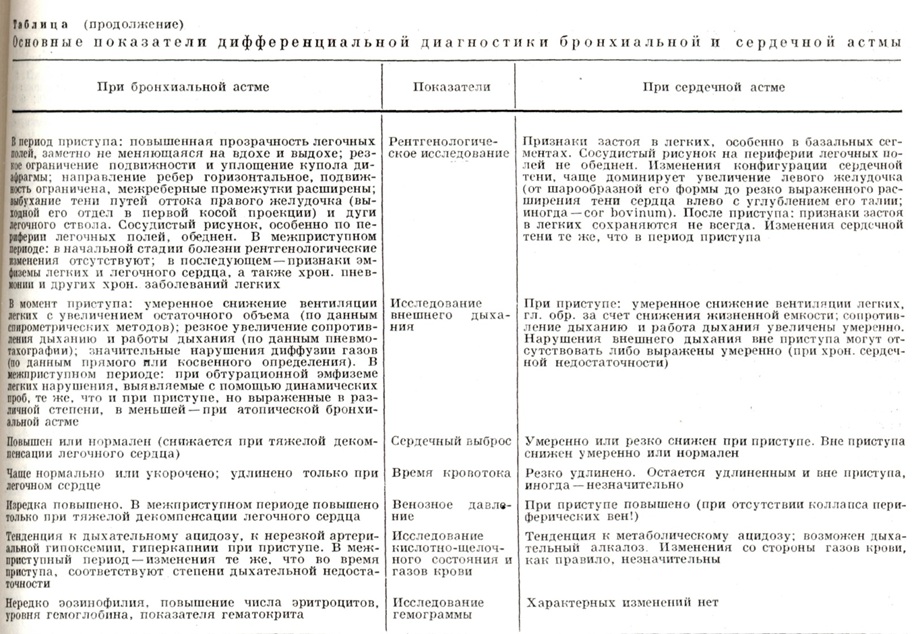

Часто Б. а. необходимо дифференцировать с сердечной астмой (см. табл. Основные показатели дифференциальной диагностики бронхиальной и сердечной астмы). Важным моментом в дифференциальной диагностике является анамнез. Указания на артериальную гипертонию, коронарную недостаточность, перенесённый инфаркт миокарда, клапанные поражения сердца, а также отмечаемые при объективном исследовании увеличенные размеры сердца и печени, отеки и другие симптомы говорят в пользу сердечной астмы (см.). Особенно труден дифференциальный диагноз, когда при Б. а. наступает декомпенсация по правожелудочковому типу.